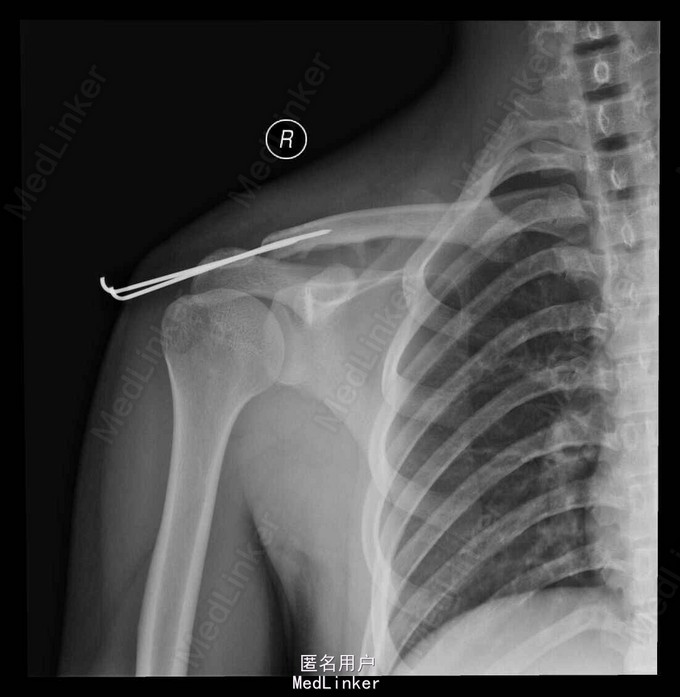

诊断:右锁骨远端陈旧性骨折伴肩锁关节脱位肩锁关节 治疗: 右锁骨远端骨折切开探查骨块摘除,肩锁关节脱位复位克氏针固定,喙锁韧带重建术

悬吊4-6周, 3月内避免右上肢负重及过度活动;术后6-8周视复查情况予以克氏针拔除;